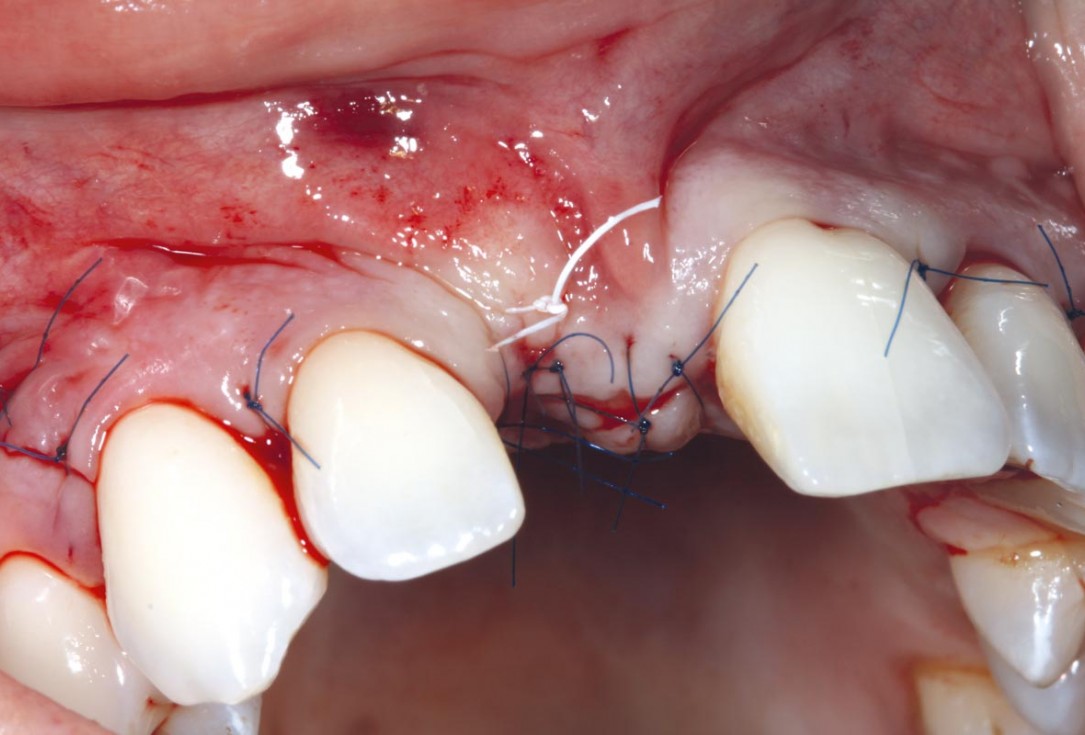

6/11 - Horizontal matress suture and tension-free wound closuremaxgraft® cortico at combined defect palatally and facially - Dr. K. Höckl

7/11 - Healing after 10 daysmaxgraft® cortico at combined defect palatally and facially - Dr. K. Höckl